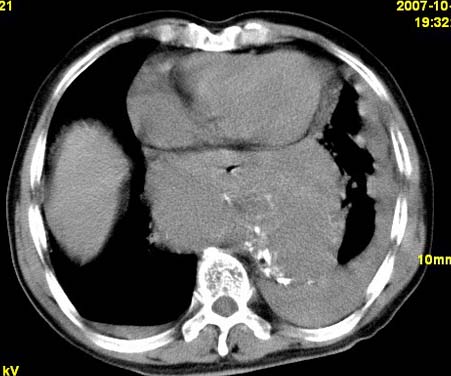

标题: CT10190:男,70,胸部疼痛数年,加重一天。典型病例。 [打印本页]

标题: CT10190:男,70,胸部疼痛数年,加重一天。典型病例。

典型降主动脉瘤伴血栓形成.瘤体下部局部边缘不清,结合病史,不除外局部撕裂外渗可能.另左侧胸水,肺部压迫不张改变.建议增强进一步检查.

典型降主动脉瘤伴血栓形成。支持:降主动脉瘤!

考虑胸主动脉瘤并血栓形成,胸腔积液

1.降主动脉瘤伴血栓形成.2.左侧胸腔积液,考虑为主动脉瘤破裂所致。

降主动脉明显增粗,边缘模糊,周围低密度影,双侧胸膜腔少量积液,结合临床考虑胸主动脉瘤破裂并双侧胸腔积液。